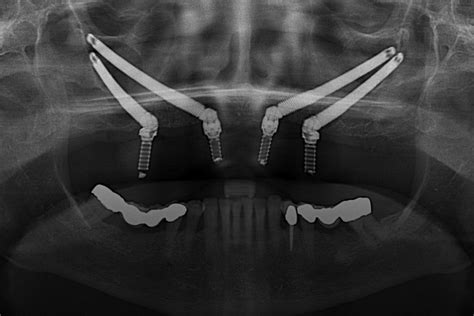

Implantes dentales cigomáticos

Para compensar la falta de hueso maxilar se pueden emplear implantes de un tamaño mayor que irán sujetos en el hueso cigomático. Para aquellos pacientes con una pérdida ósea considerable en el maxilar superior, los implantes zigomáticos ofrecen una alternativa confiable. Estos implantes se colocan en el hueso cigomático (el hueso del pómulo), que suele tener mayor densidad y volumen en comparación con el hueso maxilar.

Estos implantes se fijan en el maxilar superior, en un ángulo de 45-55°.

Se fijan en el hueso cigomático (pómulo), una zona más densa que suele mantenerse incluso cuando hay pérdida en el maxilar superior. Suelen utilizarse en casos de reabsorción severa.

Una de las ventajas de este tipo de implantes es que ofrecen una solución cuando las opciones tradicionales no son viables. Sin embargo, también tienen limitaciones y un mayor riesgo de complicaciones (infecciones respiratorias, sinusitis…) en comparación con los implantes endoóseos.

Se insertan en el hueso pterigoideo, que está situado en la parte posterior de la cavidad nasal y cerca del hueso cigomático (pómulo).